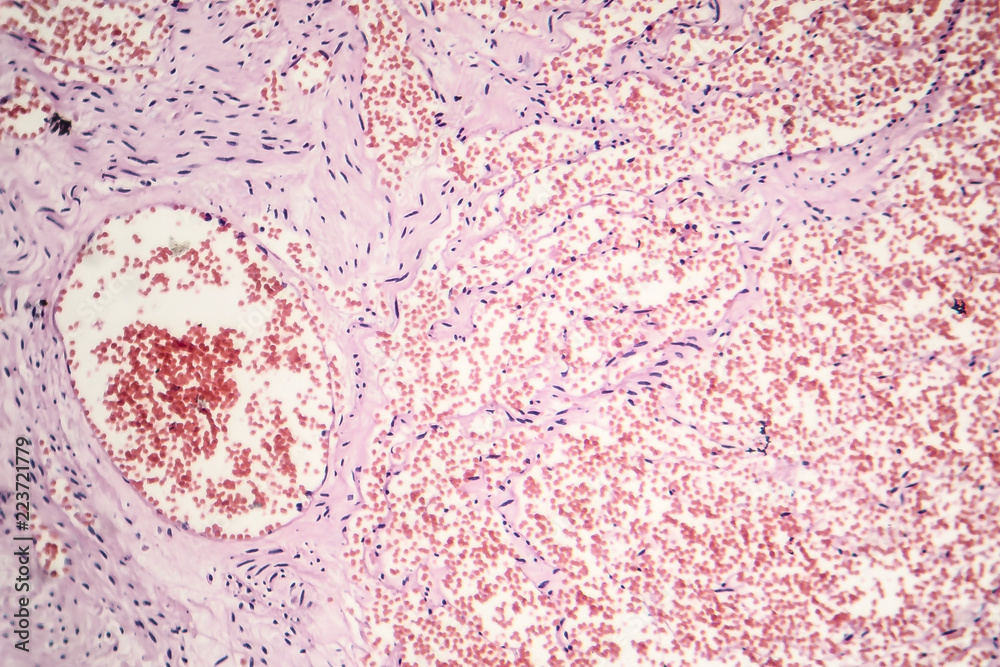

Histología

Consiste en acúmulos de células endoteliales en dermis o en tejido subcutáneo (a veces en ambos). Se diferencia del hemangioma cavernoso por una disposición más superficial y una mayor proliferación endotelial.